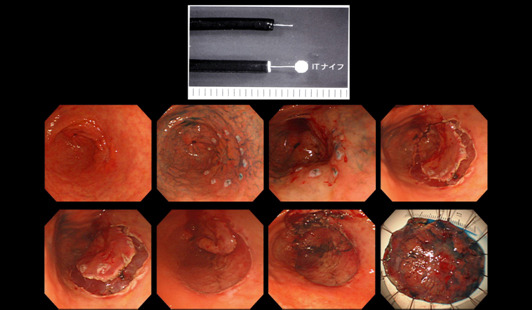

위암, 조기위암 선별

조기 위암은 내시경적 절제술만으로도 완치가 가능한 경우가 많기 때문에 최대한 이른 시기에 발견하는 것이 중요합니다.

육안 소견만으로는 정상 점막과 거의 구별이 안 되는 경우가 많아,

- 색조의 미세한 차이

- 얕은 함몰

- 표면 패턴 변화

등을 근거로 조직검사를 시행합니다. 이 단계에서의 조직검사는 생명 예후와 직결되는 진단 과정입니다.